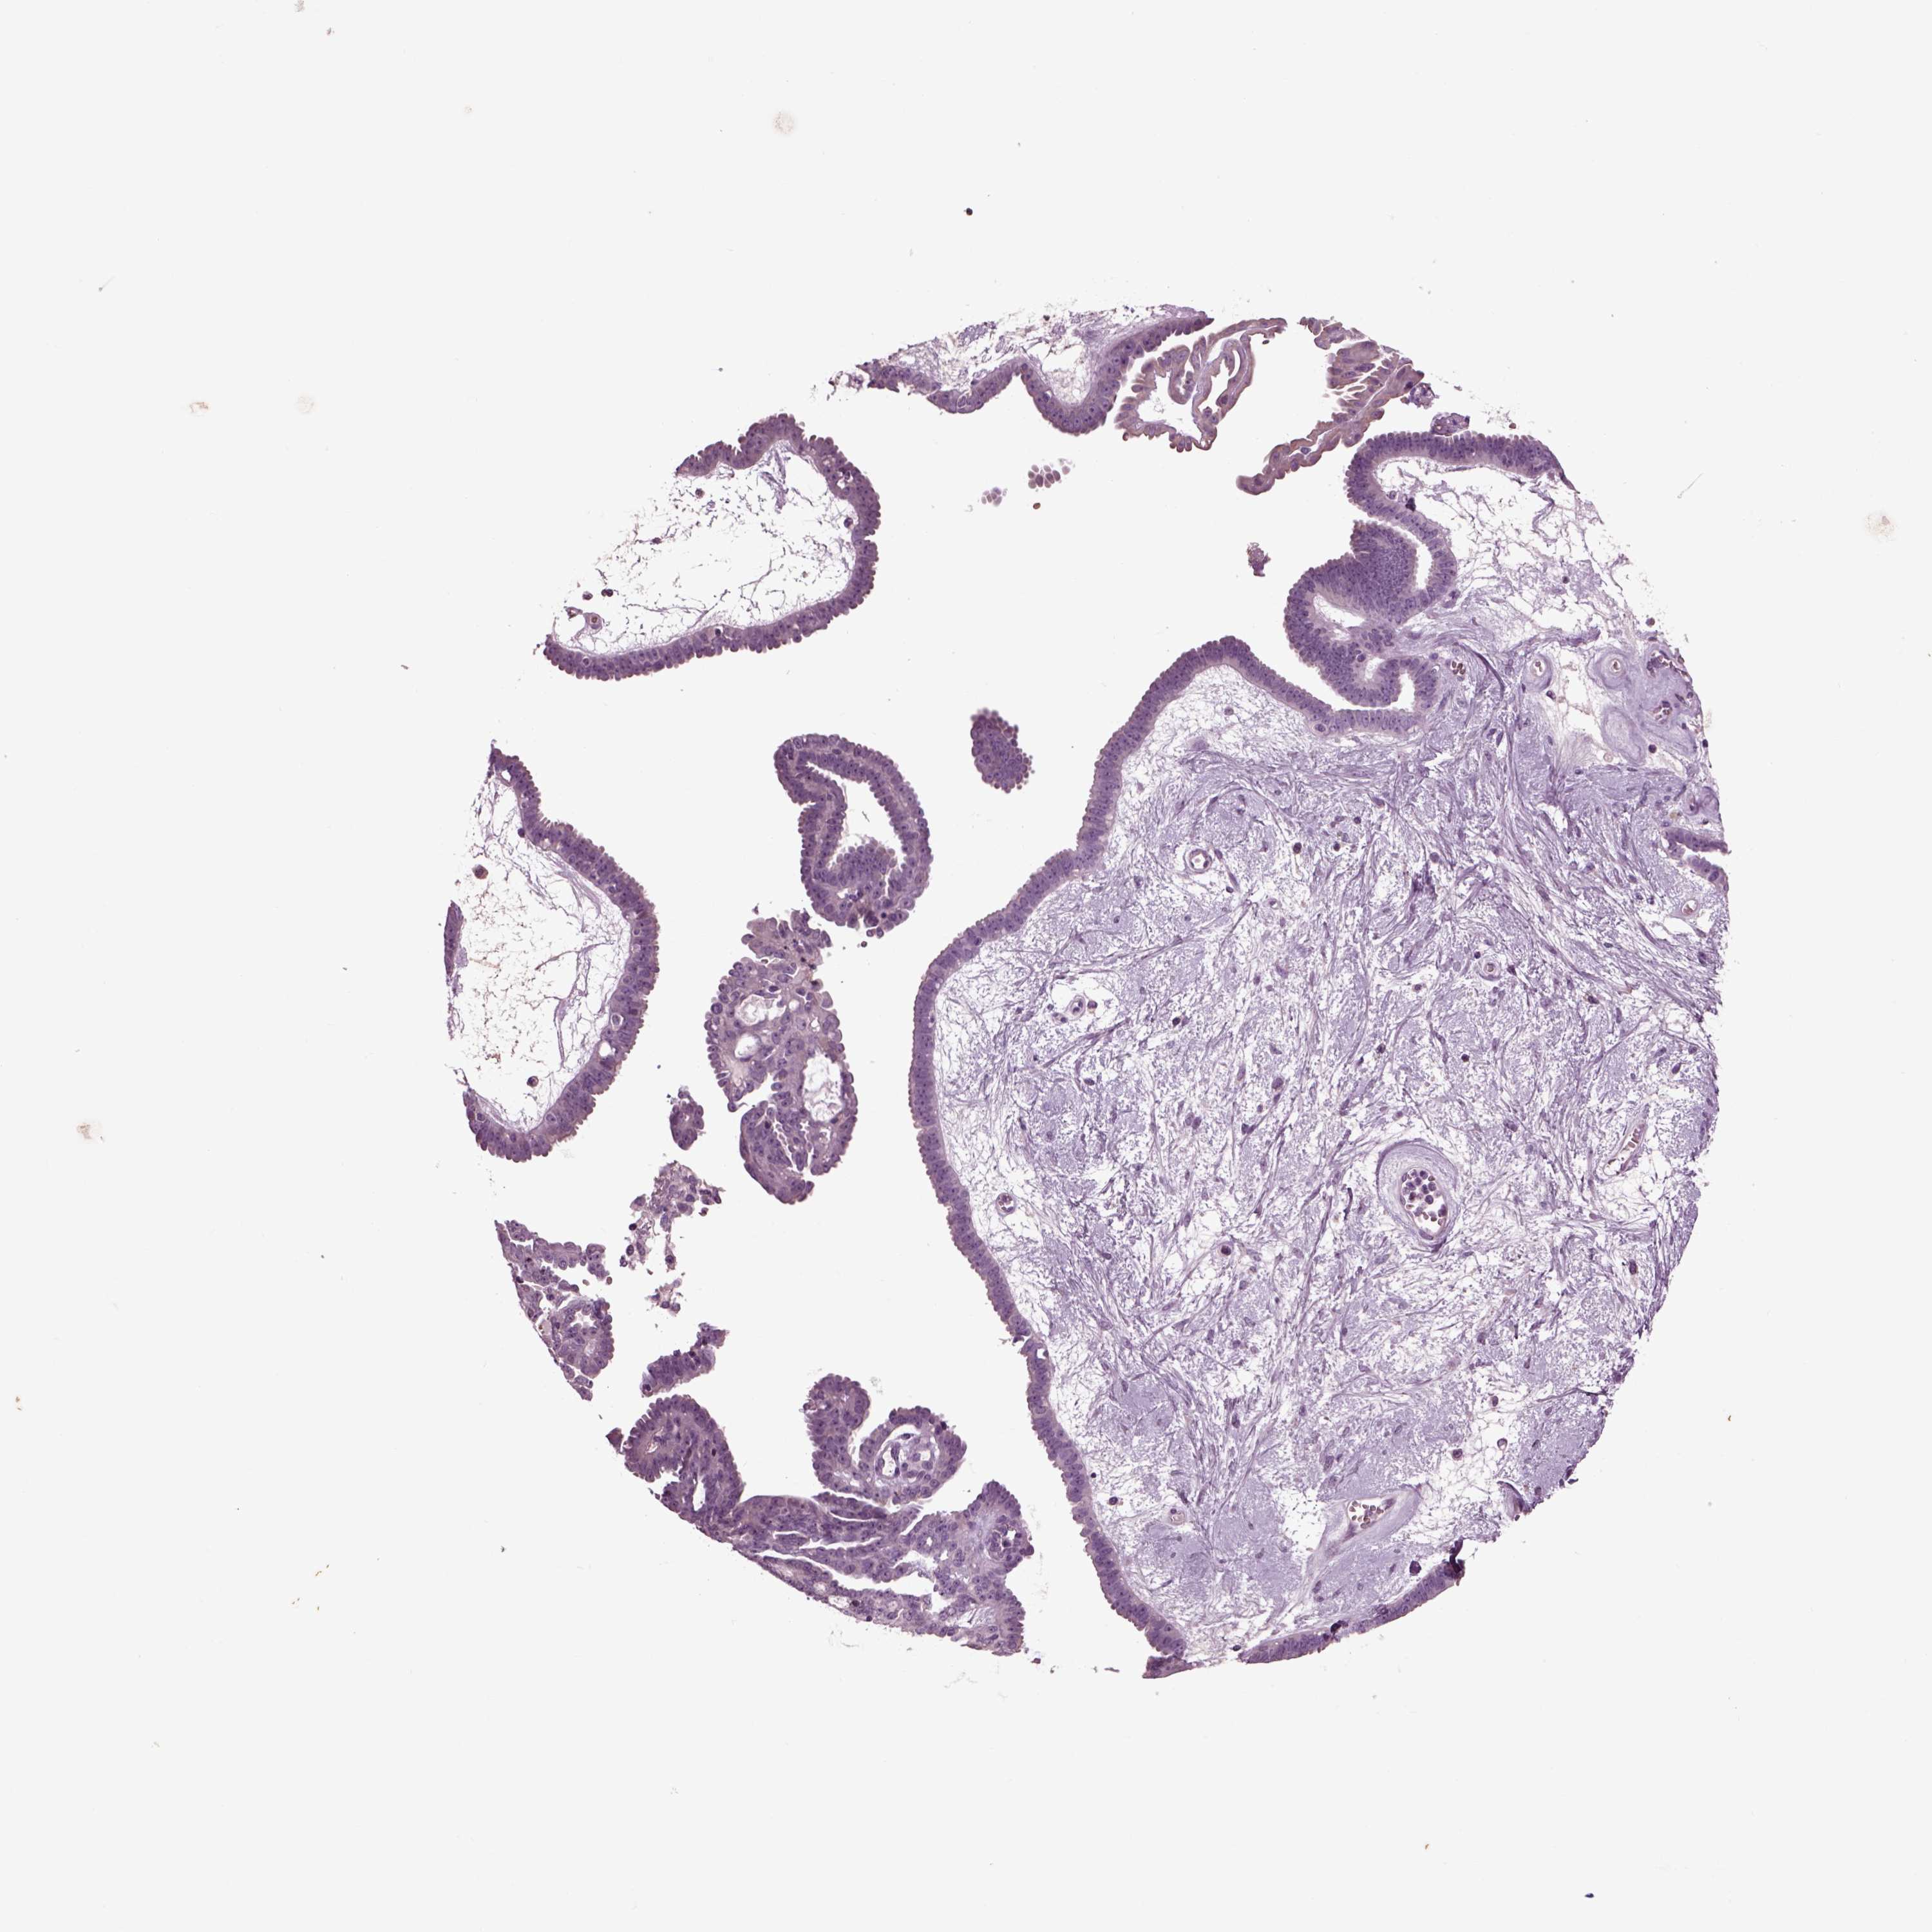

OVARIAN CANCER - Protein expressioni

A mouse-over function shows sample information and annotation data. Click on an image to view it in a full screen mode. Samples can be filtered based on level of antibody staining by selecting one or several of the following categories: high, medium, low and not detected. The assay and annotation is described here.

Note that samples used for immunohistochemistry by the Human Protein Atlas do not correspond to samples in the TCGA dataset.

Antibody stainingi

Antibody staining in the annotated cell types in the current human tissue is reported as not detected, low, medium, or high, based on conventional immunohistochemistry profiling in selected tissues. This score is based on the combination of the staining intensity and fraction of stained cells.

Each image is clickable and will lead to virtual microscopy that enables deeper exploration of all samples and also displays staining intensity scores, fraction scores and subcellular localization as well as patient and tissue information for each sample.

Antibody HPA008759

Antibody HPA012602

Antibody CAB009403

Cystadenocarcinoma, serous, NOS

Cystadenocarcinoma, mucinous, NOS

Carcinoma, endometroid